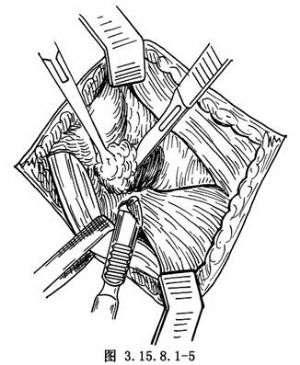

切开皮肤、筋膜组织,不要做皮下浅层分离,防止皮肤坏死。沿切口方向切开踝前十字韧带(图3.15.8.1-4),切口下方的腓骨长短肌腱向下牵拉,将伸趾短肌自跟骨前外侧起点剥离,向远侧翻转,显露跗骨窦,其内有脂肪组织是距跟关节标志(图3.15.8.1-5),清除后切断跟距间韧带,显露距(下)跟关节(图3.15.8.1-6)。在切口上方向前拉开伸趾长肌,在跟骨前即跟骰关节,距骨远端即距舟关节,切开关节囊,足内翻、内收,三个关节都能清楚显露(图3.15.8.1-7)。